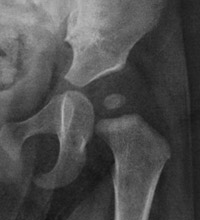

Dislocated or dislocatable - the hip socket is not deep and the ball is either sitting outside the socket (dislocated) or it is easily pushed out of the socket (dislocatable). |

![]() |